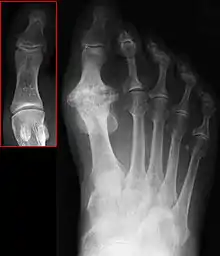

| Hallux not labeled but visible at upper left. | |

Hallux rigidus or stiff big toe is degenerative arthritis and stiffness due to bone spurs that affects the metatarsophalangeal joints (MTP) at the base of the hallux (big toe).